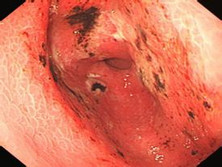

在医院里,医生仔细询问了我的症状和生活习惯,然后安排了一系列检查。等待的时间里,我心里有点忐忑,不知道结果会是怎样。终于,医生告诉我,出血的原因可能是消化道溃疡引起的,需要进行进一步治疗。

医生的话让我松了一口气,虽然病情还需要继续观察和治疗,但至少知道了原因。在医生的建议下,我开始规范饮食,多吃易消化的食物,少吃辛辣刺激食物,同时按时服用药物。